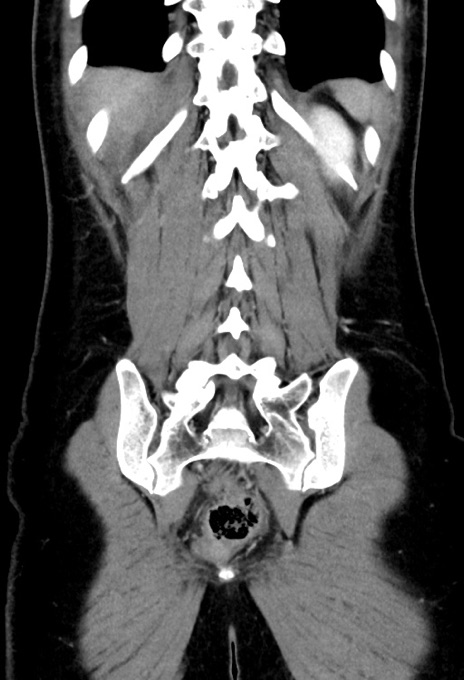

横断像